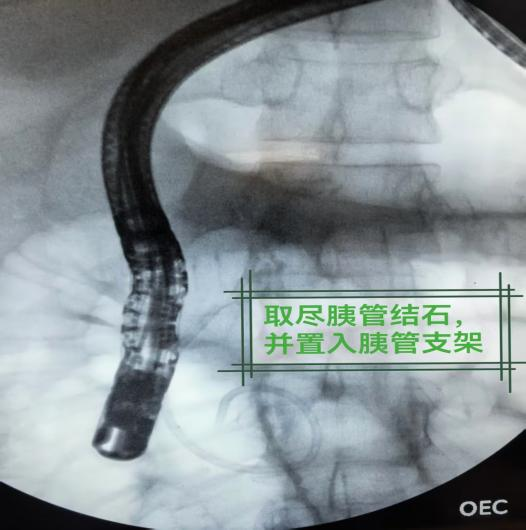

针对这一情况,消化内科胆胰组采用ERCP(经内镜逆行胰胆管造影)技术为小杨实施微创手术,成功取出结石的同时,还放置了一个临时支架以保障胰管通畅。术后两三天,小杨的腹痛腹胀基本消失,第四天顺利出院,困扰他多年的病痛被根除。